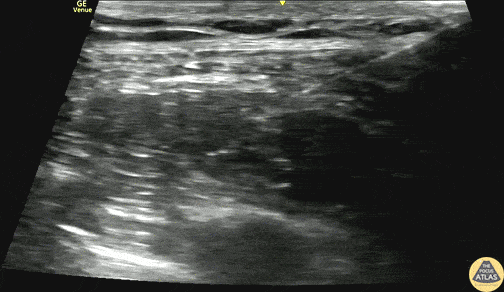

20s F presented with chest pain after a trigger point injection to the back at a chiropractic appointment, found to have a large pneumothorax. To facilitate analgesia for chest tube placement, a serratus anterior plane block was performed under ultrasound guidance. Seen here, the needle is entering from the posterior aspect, and deposits anesthetic in the plane between serratus anterior and latissimus dorsi. The patient had improved pain and was able to have a tube thoracostomy performed, and she was admitted for further observation. Dr. Mark Serpico, PGY3 and Dr. Molly Thiessen, Ultrasound Fellowship Director Denver Health Residency in Emergency Medicine